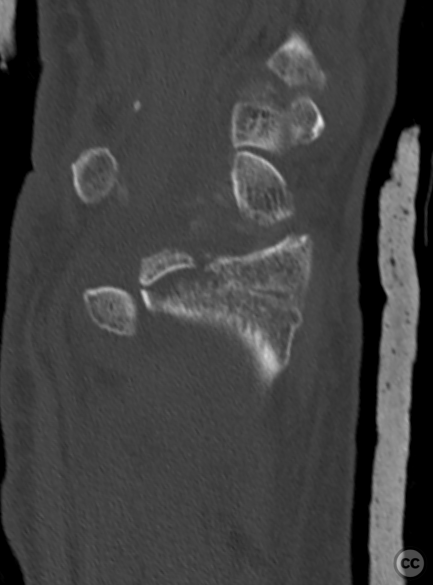

Clinical and radiological findings:  A 72-year-old female sustained a multifragmentary, dorsally displaced distal radius fracture after a fall down stairs. Initial reduction revealed a 180-degree flipped fragment of the volar ulnar articular margin, unreducible by closed means. There was no mention of associated neurovascular compromise or open injury. Radiographs and intraoperative fluoroscopy confirmed the presence of a multifragmentary intra-articular fracture (AO/OTA 23-C3), with a flipped volar ulnar fragment and radial styloid impaction. The distal radioulnar joint alignment was restored postoperatively.

Planning remarks:  The preoperative plan was for open reduction and internal fixation via an Extended (eFCR) volar approach, with specific attention to direct visualization and reduction of the flipped volar ulnar articular fragment, anatomical reduction of the radial styloid, and fragment-specific fixation using mini-fragment plates and provisional Kirschner wires.

The flipped volar ulnar articular margin fragment was irreducible by closed means due to capsular attachment and required direct open de-rotation and fixation. The impaction and proximal displacement of the radial styloid fragments were challenging due to persistent traction from musculus brachioradialis and scaphoid pressure; ligamentotaxis using Kirschner wire spreader over the scaphoid facilitated reduction. Fragment-specific fixation was necessary: a custom-shaped hook plate for the volar ulnar lip fragment provided stable fixation and prevented dorsal instability, while a separate T-plate addressed the radial styloid. Bicortical locking screws were used to secure both plates, with some screws engaging dorsal fragments from the volar side. Careful adaptation of pronator quadratus over hardware minimized risk of musculus flexor pollicis longus irritation. Additional suture stabilization of radiocarpal ligaments to pronator quadratus provided secondary ligamnetal support.